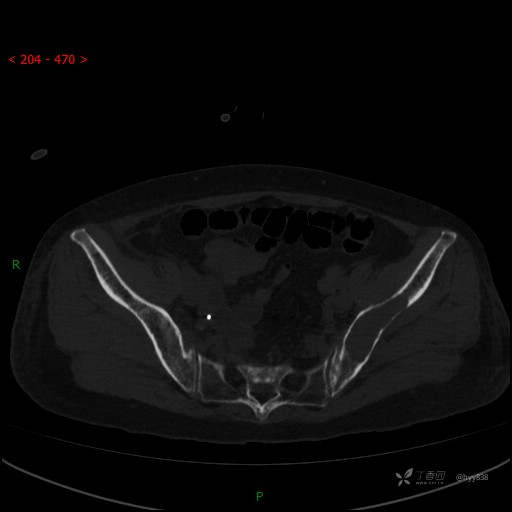

CT平扫

骨窗